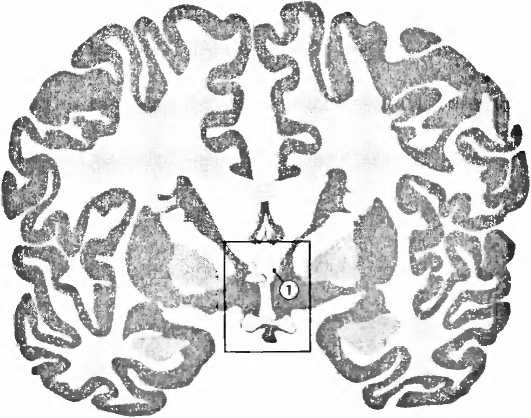

Рис. 9. В базальном отделе боковых желудочков (ventriculi laterales), выше ростральнее и медиальное миндалевидного тела, лежит (1) опорное ядро концевой полоски (bed nucleus of stria terminalis, BST), маленькая область мозга, существенная для сексуального поведения.

Все данные указывают на то, что гендерные проблемы возникают уже во время пребывания в матке. Были найдены небольшие изменения в генах, причастных к воздействию гормонов на развитие мозга, которые повышают вероятность транссексуальности. Ненормальный уровень гормонов плода или медикаменты, которые женщина принимает во время беременности и которые препятствуют расщеплению половых гормонов, могут увеличивать вероятность транссексуальности. Сексуальная дифференциация половых органов происходит в первые месяцы беременности, а сексуальная дифференциация мозга — на второй стадии. Поскольку оба эти процесса происходят в разные периоды времени, существует теория, что при транссексуальности они протекают независимо друг от друга и подвергаются различным влияниям. Если это так, то у М—>Ж транссексуалов следовало ожидать наличия фемининных структур в маскулинном мозге, а у Ж—>М гранссексуалов — наоборот. В 1995 году мы действительно обнаружили такую инверсию полового различия в одной небольшой структуре в мозге посмертных доноров. Результаты нашей работы были опубликованы в журнале Nucure. Речь шла об опорном ядре концевой полоски (bed nucleus of stria terminalis, BST) в гипоталамусе, маленькой структуре, причастной к многим аспектам нашего сексуального поведения (рис. 9, 10). Центральная часть этого ядра (BSTc) у мужчин вдвое больше и содержит вдвое больше нейронов, чем это наблюдается у женщин. У М—>Ж транссексуалов мы обнаруживаем женскую BSTc. Единственный мозг одного Ж—>М транссексуала, который мы могли изучать, — материал, всё еще более редкий, чем мозг М—>Ж транссексуалов, — имел действительно мужскую BSTc. Так что мы могли исключить то, чао инверсия половой дифференциации мозга транссексуалов была вызвана изменением уровня гормонов во взрослом состоянии. Инверсия, таким образом, должна была иметь место в период развития мозга.